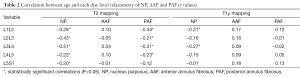

Figure 4 shows a graphical representation of the relationship between the relaxation times obtained by relaxometry maps and the subject characteristics. There was a negative correlation between age and T2 relaxation time (r=−0.30, P<0.0001) and a positive correlation between disc volume and relaxation time T2 (r=0.15, P=0.002) (Table 3).

Full table

As shown in Table 4, we observed a negative linear correlation between T2 relaxation times and age at all lumbar disc levels (P<0.02 at all levels). There was no correlation between age and volumetry for any disc (P>0.07 at all levels). We also observed no relationship between age and T1ρ values for any disc level (P>0.06 at all levels). BMI, height and weight were not correlated with any lumbar IVD relaxometry measurement.

Full table